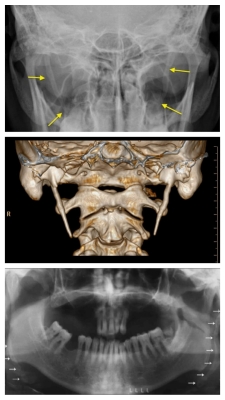

De longe o melhor exame de imagem para diagnosticar a Síndrome de Eagle é a tomografia computadorizada — especialmente a tridimensional (importantíssima “para determinar a localização, o tamanho, a forma, a angulação e a proximidade com estruturas neurovasculares”). “No entanto, uma radiografia simples do crânio (visão ou método de Towne) também é útil no reconhecimento”. É possível visualizar a calcificação numa radiografia cervical de perfil, mas fica um pouco mais difícil numa A-P ou “Boca Aberta” (transoral). Já uma radiografia extrabucal panorâmica da arcada dentária parece ser bem eficaz (daí a frequência e relativa facilidade dos dentistas para diagnosticar tal afecção). Exemplos de calcificação do ligamento estilo-hióideo podem ser visualizados nas incidências abaixo: